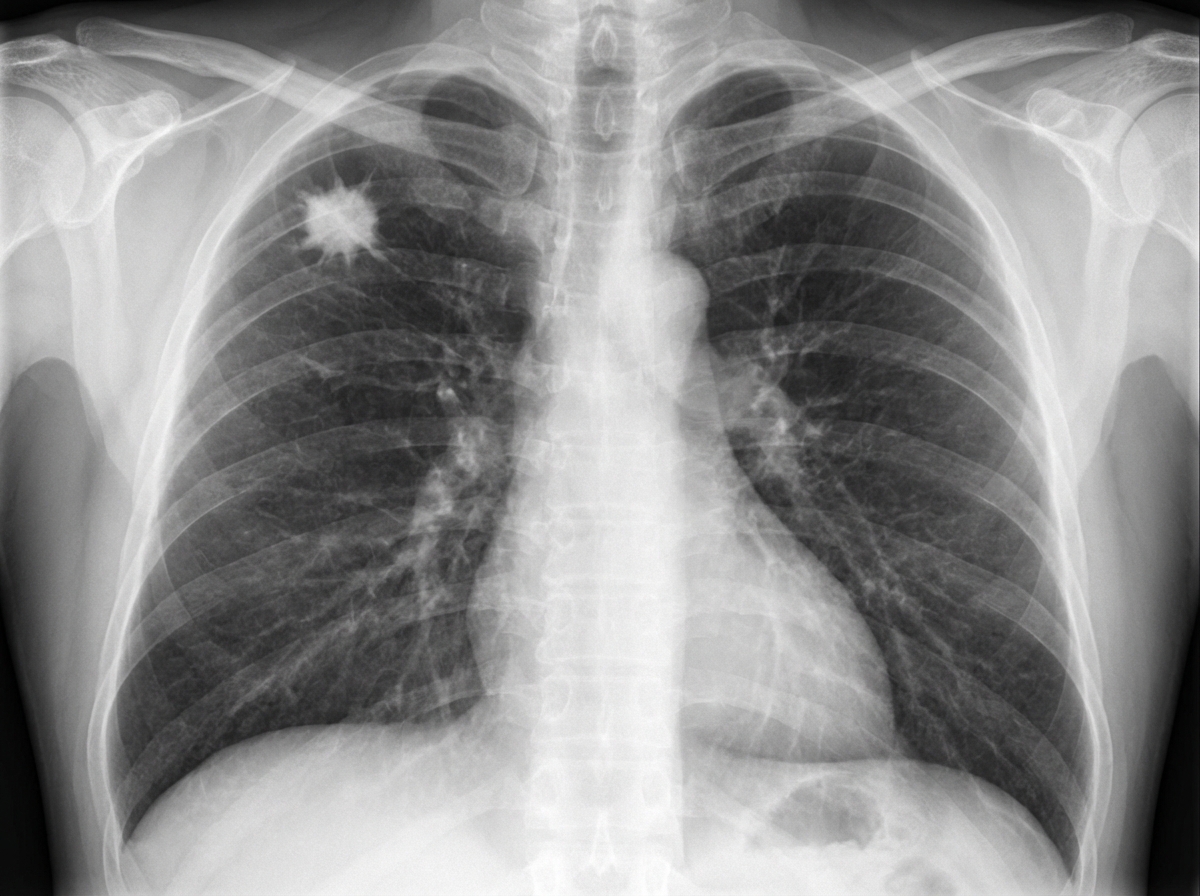

A 62-year-old man comes to the physician because of a persistent cough for the past 2 weeks. During this time, he has also had occasional discomfort in his chest. Three weeks ago, he had a sore throat, headache, and a low-grade fever, which were treated with acetaminophen and rest. He has a history of hypertension and hyperlipidemia. His father died of myocardial infarction at the age of 57 years. He has smoked a pack of cigarettes daily for the past 40 years. Current medications include enalapril and atorvastatin. His temperature is 37°C (98.6°F), pulse is 70/min, and blood pressure is 145/90 mm Hg. Physical examination shows no abnormalities. An x-ray of the chest is shown. Which of the following is the most appropriate next step in management?